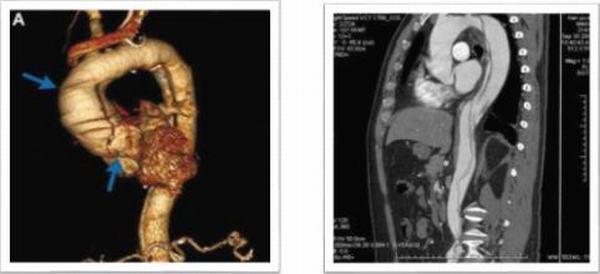

第一例患者31歲女性,運(yùn)動(dòng)員,有外傷史;主訴“反復(fù)胸痛2月,加重1小時(shí)”入院,入院后行主動(dòng)脈CTA提示:升主動(dòng)脈增寬,最寬處10.7cm,升主動(dòng)脈近主動(dòng)脈根部多發(fā)破口,最大破口直徑5.1cm,最小破口直徑0.64cm,主動(dòng)脈夾層動(dòng)脈瘤(A型)。心臟彩超:主動(dòng)脈夾層(A型)伴主動(dòng)脈瓣關(guān)閉不全,EF 50%,真腔內(nèi)血流進(jìn)入假腔,主動(dòng)脈瓣反流(大量)。心肌損傷標(biāo)志物正常,行術(shù)中探查破口累及主動(dòng)脈弓部及降部,手術(shù)方案:升主動(dòng)脈人工血管置換、主動(dòng)脈弓置換、降主動(dòng)脈支架植入、主動(dòng)脈瓣機(jī)械瓣膜置換手術(shù)順,利,術(shù)后第二天拔除氣管插管,第12天出院。

第二例患者36歲男性,職員,馬凡氏綜合癥;主訴“后背部疼痛3小時(shí)”入院,8年前因“馬凡氏綜合征、升主動(dòng)脈瘤并主動(dòng)脈伴關(guān)閉不全”在我科行Bentall手術(shù);入院后行主動(dòng)脈CTA提示:主動(dòng)脈夾層動(dòng)脈瘤(B型)合并主動(dòng)脈弓瘤樣擴(kuò)張,直徑7.0cm,主動(dòng)脈弓至左髂總動(dòng)脈雙腔影,內(nèi)膜片撕裂,并見(jiàn)多發(fā)破口,左側(cè)鎖骨下動(dòng)脈起始部受累,破口內(nèi)徑約0.83-1.28cm,腹腔干起自真假腔,腸系膜上動(dòng)脈假腔;左腎動(dòng)脈起自假腔,右腎動(dòng)脈起自真假腔;該病例為二次手術(shù)患者,且為夾層動(dòng)脈瘤伴弓部瘤樣擴(kuò)張。擬行全主動(dòng)脈弓置換、降主動(dòng)脈支架植入術(shù),手術(shù)順利,術(shù)后第二天拔除氣管插管,第14天出院,恢復(fù)良好。

第三例患者59歲男性,農(nóng)民,有“腹部疼痛7小時(shí),右下肢麻木5小時(shí)”入院,既往患有高血壓病10余年,腦出血病史8年;在當(dāng)?shù)乜h醫(yī)院行胸部增強(qiáng)CT提示:主動(dòng)脈夾層動(dòng)脈瘤(A型);救護(hù)車急診送來(lái)我院,急查主動(dòng)脈CTA:主動(dòng)脈夾層I型(主動(dòng)脈全程受累及)。心臟彩超:主動(dòng)脈夾層動(dòng)脈瘤(I型),主動(dòng)脈瓣關(guān)閉不全,心包積液(少量),血流往返于真腔與假腔之間,主動(dòng)脈瓣反流(大量)。該病例擬行Bentall、全主動(dòng)脈弓置換、降主動(dòng)脈支架植入術(shù),手術(shù)順利,術(shù)后第11天出院,恢復(fù)良好。